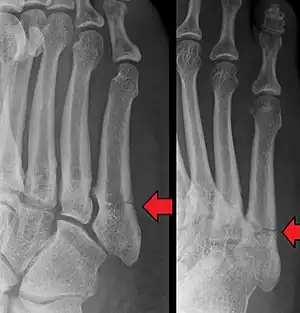

![]() | |

| Jones fracture as seen on Xray | |